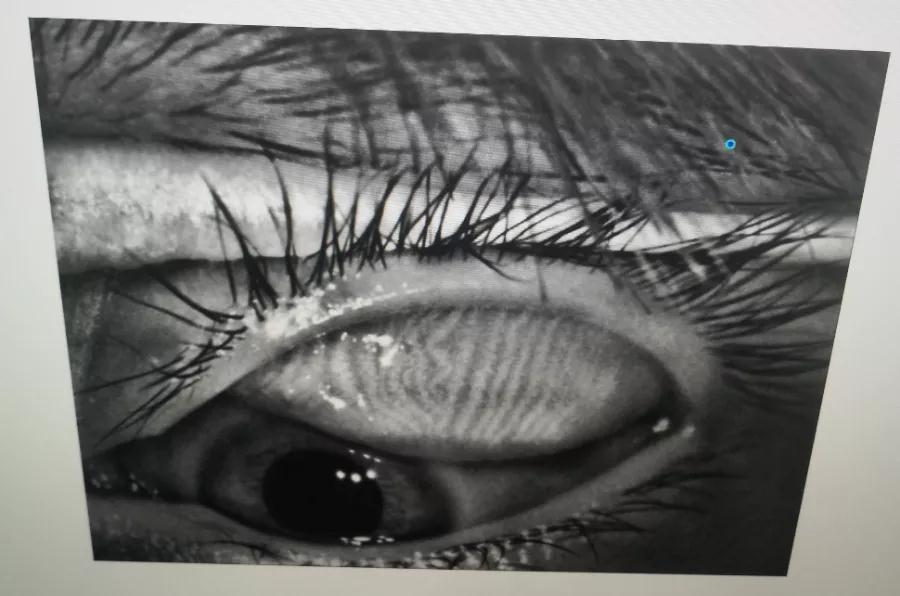

瞼板腺是排列在我們上下眼皮里面,分泌油脂的腺體,這些油脂是組成淚液的重要成分,可以讓淚水更長(zhǎng)時(shí)間的停留在眼球表面。瞼板腺油脂減少,淚水蒸發(fā)就會(huì)加快,眼球暴露在外的時(shí)間變長(zhǎng),會(huì)加重眼睛干澀,時(shí)間一久,干眼也就隨之而來(lái)。

通過(guò)熱敷并按摩擠壓上下眼瞼,將瞼板腺內(nèi)不能自行排出的分泌物推出,疏通堵塞的瞼板腺開(kāi)口。

熱敷可以促進(jìn)眼周部位的血液循環(huán),瞼板腺按摩能有效改善瞼板腺功能,解決絕大多數(shù)干眼患者油脂分泌不足問(wèn)題。

03、OPT強(qiáng)脈沖光

通過(guò)強(qiáng)脈沖光高溫消除蠕形螨蟲(chóng),同時(shí)脈沖光產(chǎn)生的熱量可以熔解軟化瞼酯,改善瞼板腺內(nèi)脂質(zhì)分泌物的流動(dòng)性,疏通瞼板腺,提高淚膜的穩(wěn)定性,恢復(fù)正常眼表功能和眼部“鎖水”能力,從病因上治療干眼。